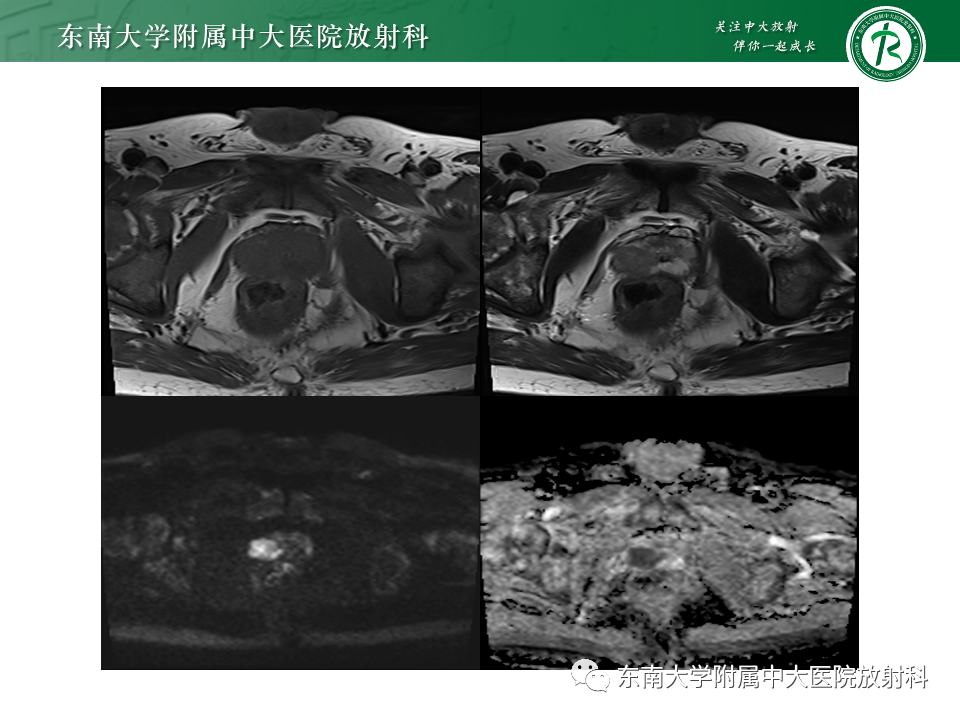

病史

男,68岁,发烧伴肛周疼痛1月

既往史:10月前于外院行“直肠癌根治术”,病理为中分化腺癌

B超提示:前列腺左侧叶低回声团,占位?